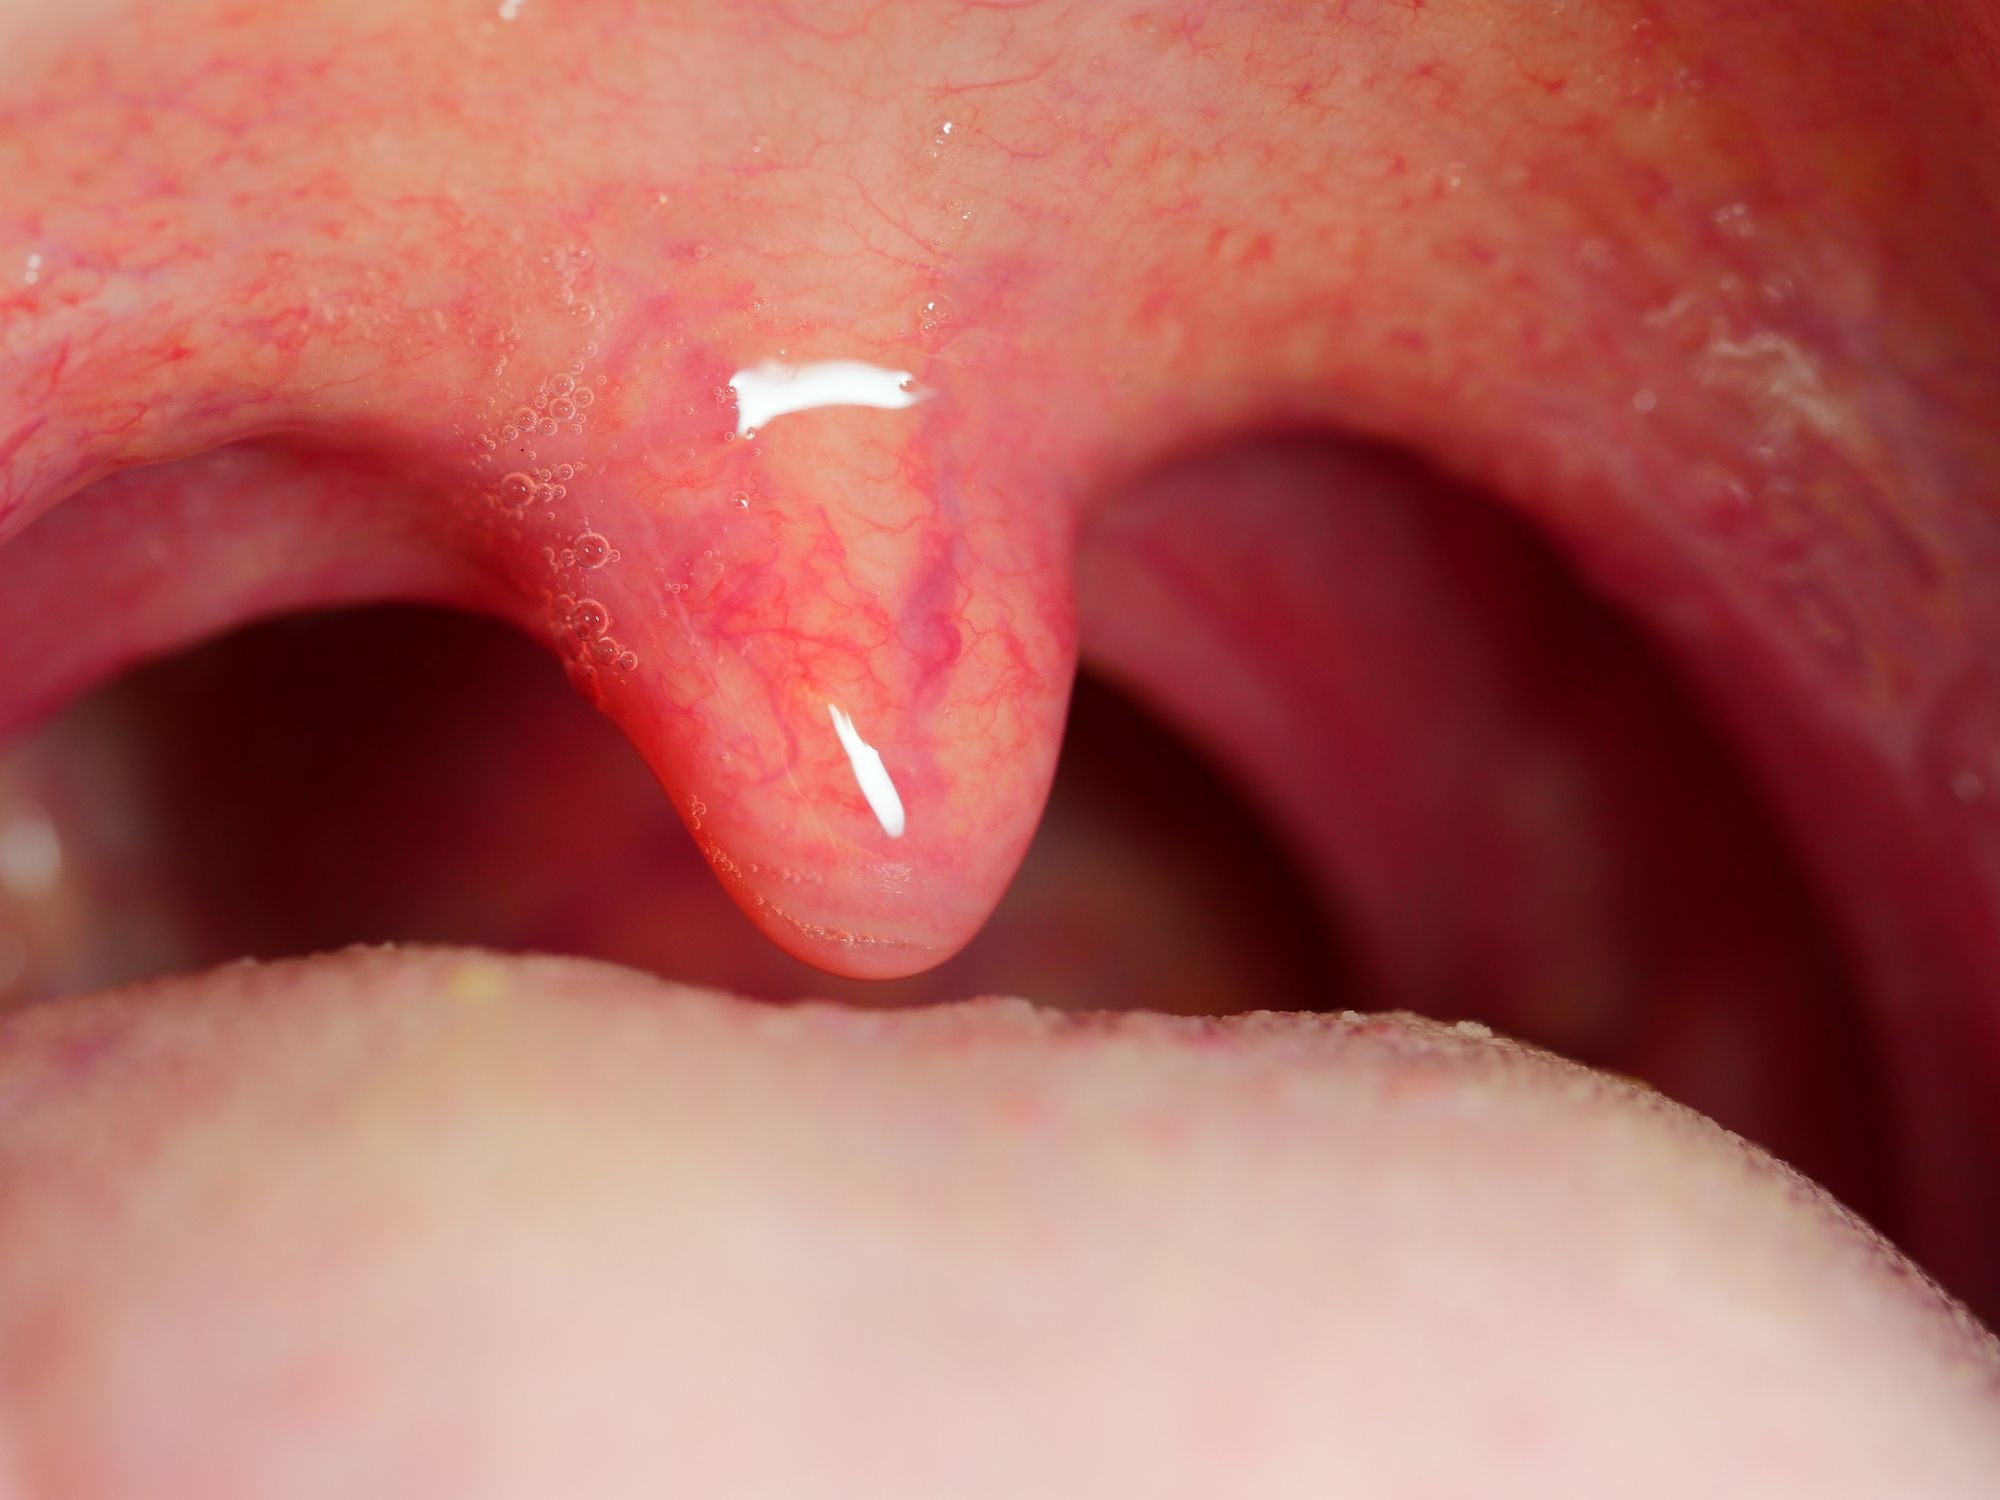

What causes a swollen uvula?

The uvula is made up of mucous membranes, connective and muscle tissue, as well as canals that excrete saliva. It is very flexible, which ensures that it can fulfill its functions.

Though rare, the uvula and the surrounding areas can become swollen. Redness, soreness, and inflammation of the uvula is called uvulitis.

With uvulitis, a person may feel as if something is stuck in the back of their throat as well as experience difficulty swallowing. In some cases, the sound of the voice may also be affected.